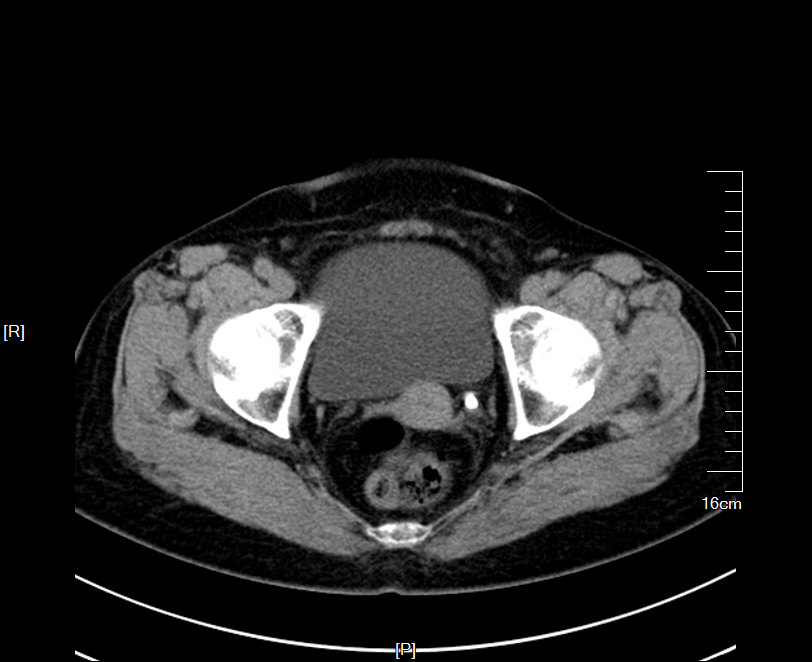

2016年09月手术患者,男性,83岁,太仓人,双侧腰酸不适五年伴体检发现双侧输尿管结石一周入院,五年来患者自觉双侧腰酸,一直未予重视,近期自觉双下肢浮肿且左侧腰痛明显加剧,遂参加社区免费体检时发现双侧输尿管结石遂来院就诊,CT:右肾萎缩无功能,左侧肾脏代偿性增大,左肾积水扩张,双侧输尿管结石,左侧约1.5cm,右侧约2.0cm GFR:左侧41.27ml/min,右侧5.2ml/min。肾功能:Cr 571umol/L;术前诊断:双侧输尿管结石 右肾萎缩 右肾无功能 左肾积水,鉴于右输尿管结石梗阻时间太长,右肾已几乎无功能,萎缩固缩,且肾功能已失代偿,遂只能急症先输尿管镜处理左输尿管结石,保护左侧肾脏,待肾功能稳定后再处理右侧输尿管结石及右肾,患者预后不容乐观。

CT检查提示:右肾萎缩无功能,左侧肾脏代偿性增大,左肾积水扩张,双侧输尿管结石